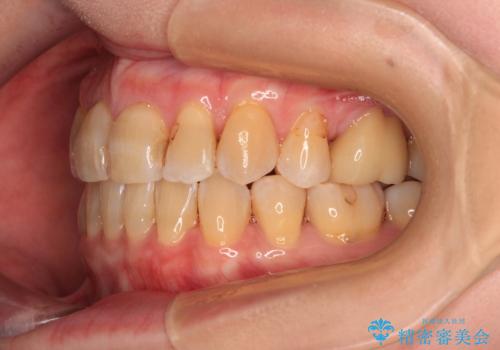

- 口元の突出感を気にして来院された患者様です。

上下前歯が著しく前突している状態であったので、上下左右の小臼歯4本を抜歯し、ワイヤー装置にて矯正治療を行うこととしました。

上顎左側は第二小臼歯に大きなむし歯があったため、通常は第一小臼歯を抜歯するところ、イレギュラーに第二小臼歯を抜歯することとしました。

抜歯する第二小臼歯の後方の歯は神経近くにまで及ぶむし歯があったため、事前に処置をしておき、矯正治療後にオールセラミッククラウンにて補綴治療を行うこととしました。